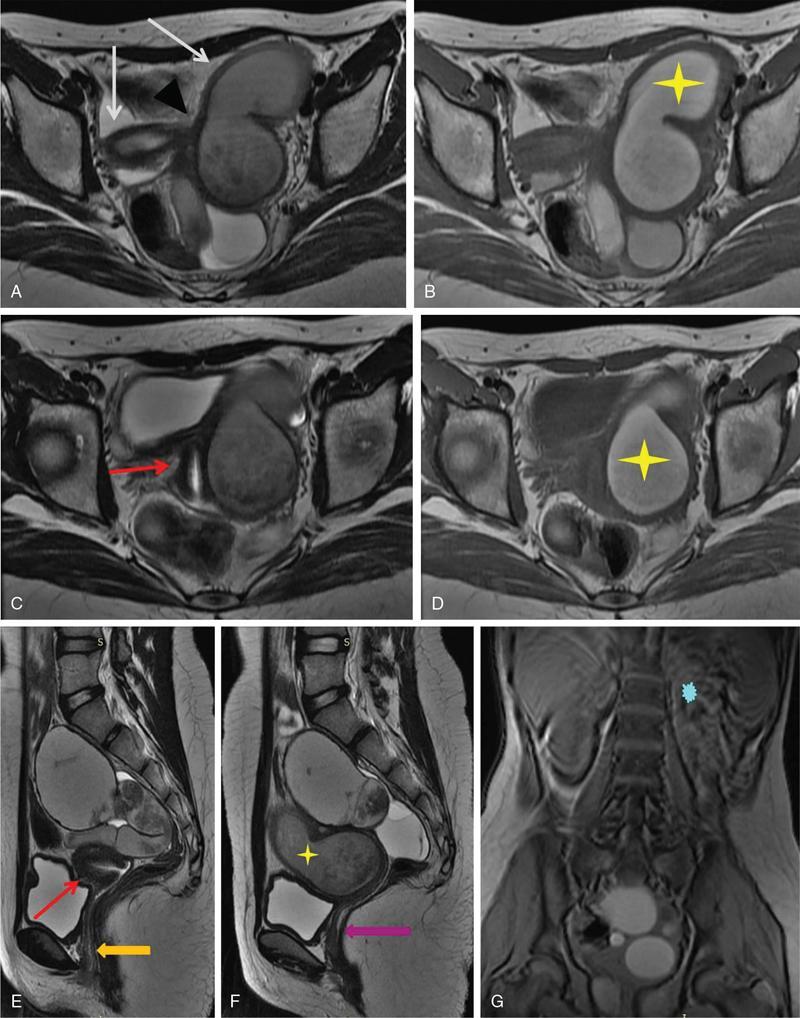

MÜLLERIAN DUCT ANOMALIES Rajani Gorantla Müllerian ducts are a pair of tubular structures that give rise to uterus, cervix, fallopian tubes and upper two-thirds of vagina. Disruption or failure of normal development can result in occurrence of Müllerian duct anomalies (MDAs). These are commonly associated with other congenital anomalies of urinary tract and ovaries due to the close relationship between the development of mesonephric and paramesonephric ducts; few patients also have associated skeletal system anomalies. The prevalence of MDAs in an unselected population was 5.5%; 8% among the infertile women, 12.3% in women with a history of recurrent pregnancy loss and 24.5% in women with miscarriage and infertility. Most of the patients with MDAs are asymptomatic and found incidentally on imaging for any other gynaecological problems, in evaluation of a patient with renal, skeletal or abdominal wall abnormalities. In symptomatic women, complains are related to the type, severity, obstructive anomaly or nonobstructive anomaly. The symptoms can be obstetric or gynaecological related, includes recurrent spontaneous abortions, infertility, preterm labour, intrauterine growth restriction and abnormal foetal lie. Few adolescent girls may present with primary amenorrhoea, hypomenorrhoea, abnormal vaginal bleeding, cyclical pain and mass. Rarely they can present with pelvic inflammatory disease with abnormal vaginal discharge, dyspareunia and urinary tract infections. The female reproductive system develops from a pair of Müllerian or paramesonephric ducts, urogenital sinus and vaginal plate. The ovaries develop separately from the primordial ridge. It is of great importance to understand the normal stages of development, as failure or interruption of any of these stages can lead to a simple to complex spectrum of anomalies. The three stages of Müllerian duct development include: At 6–10 weeks of gestation age, two paired Müllerian ducts and Wolffian ducts formation occurs. When Y chromosome factor (testicular determining factor) is absent, the Wolffian ducts undergo degeneration. The Müllerian ducts further elongate caudally and cross the Wolffian ducts to fuse in the midline. At 10–13 weeks of gestation age, caudal and lateral fusion of the two Müllerian ducts forms primitive uterovaginal canal, which is possessed of solid tissue initially located side by side and further internal canalization leads to the formation of two channels/canals divided by a septum. At this stage, there is reabsorption of the caudal septum and forms single cervical canal and vagina lumen. In around 15–20 weeks of gestation age, complete resorption of the septum takes place in a caudocranial direction from the isthmus to fundus and development of single endometrial cavity results. The fused caudal part of Müllerian ducts gives rise to the uterus, cervix and upper two-thirds of vagina; the unfused cranial part forms the fallopian tubes (Fig. 11.14.1.1). The lower vagina develops from the urogenital sinus, which is separated from the rectum by urorectal septum around 7 weeks of gestation age. The primitive uterovaginal canal embeds into the dorsal wall of urogenital sinus and forms Muller’s tubercle. Around 13 weeks of gestation, two solid masses known as sinovaginal bulbs originate from the upper part of the Muller’s tubercle, further proliferate into the caudal end of the uterovaginal canal to become a solid vaginal plate. Later canalization or degeneration of the central cells of the vaginal plate forms the lower vagina, which is usually completed by 20 weeks’ gestation. The vertical fusion of the upper and lower vagina occurs with resorption of tissue in between and forms single vaginal cavity (Fig. 11.14.1.2). The vaginal lumen is separated from the urogenital sinus by the hymenal membrane. Just before birth, the hymen normally ruptures due to retrogression of the central epithelial cells. However, a thin fold of mucous membrane persists around the vaginal introitus. The ovaries develop separately from migration of primordial germ cells to the genital ridge. Ureteric buds develop separately and concurrently. So renal anomalies are most commonly associated with MDAs with an association of 30%–50%. Various classification systems have been proposed over the past several decades to describe MDAs. Ideally, same classification system needs to be followed by a gynaecologist, surgeon and radiologist for better communication. Buttram and Gibbons classification was suggested in 1979, and it was based upon the level of failure in normal development and segregate the anomalies into groups with similar clinical manifestations, treatment, and prognosis for foetal salvage. According to Buttram and Gibbons, the uterine anomalies were classified into six classes as described in Table 11.14.1.1. The drawback is the lack of classification of vaginal and other anomalies separately. The ASRM (previously the American Fertility Society – AFS) classification system is the most widely accepted classification worldwide over the past years and was introduced in 1988. According to this classification, MDAs are classified into seven classes (class I to class VII) as mentioned in Table 11.14.1.2. However, several limitations have been described by Grimbizis and Campo in 2010 (Fig. 11.14.1.3). The drawbacks of the ASRM classification system are as follows: Hence in 2016, an updated classification of uterine septum, that is ASRM-2016 was proposed and officially approved morphometric criteria are given for distinguishing between septate, normal/arcuate and bicornuate uteri (Table 11.14.1.3). The VCUAM classification was proposed in the year 2005. The main concern is to provide a simple, systematic, clinical classification in addition to providing a precise reflection of the entire malformation. The female genital organs were divided into the following subgroups in accordance with the anatomy: vagina (V), cervix (C), uterus (U) and adnexa (A). Associated malformations were assigned to a subgroup (M) relative to each specific organ. The disadvantage is due to its inherent complexity, and more than 56,700 individual combinations of anomalies are possible. ESHRE and ESGE established a common working group named CONgenital UTerine Anomalies (CONUTA) in order to devise an improved classification system (Table 11.14.1.4). It was published in 2013. Anatomy is the basis for systemic categorization of the MDAs. The subclasses are divided by the different degrees of uterine deformity and their clinical significance (Fig. 11.14.1.4). Cervical and vaginal anomalies are classified into independent supplementary subclasses (Figs. 11.14.1.5–11.14.1.6). For most of the clinicians, it helped as starting point for the development of guidelines for their diagnosis and treatment. The malformations are graded according to severity, U0–U5, C0–C4 and V0–V4, with U5, C4 and V4 being more severe. Class U3 incorporates bicorporeal fusion defects (didelphys and bicornuate) as this was considered as a more functional mode of classification. Arcuate uterus was not included separately, but this is categorized under normal variant into class U1c. Recent studies have demonstrated that the ESHRE/ESGE system provides an effective and comprehensive classification for almost all the currently known MDAs and overcomes the limits of previous classifications. However, there is a relative overdiagnosis of septate uterus with the application of ESHRE–ESGE criteria has been reported and which potentially might lead to unnecessary surgical overtreatment. C0 C1 C2 Normal cervix Septate cervix Double ‘normal’ cervix C3 C4 Unilateral cervical aplasia Cervical aplasia U4 V0 V1 V2 V3 Normal vagina Longitudinal nonobstructing vaginal septum Longitudinal obstructing vaginal septum Transverse vaginal septum and/or imperforate hymen V4 Vaginal aplasia C MDAs’ characterization and classification is of great significance, as the treatment is determined by the type and severity of abnormality. The various imaging modalities available include: HSG was the most recognized imaging modality, earlier to the development of the ultrasonography (USG) and MRI. It is an invasive fluoroscopic-guided procedure for uterine and tubal assessment, and is performed during the midproliferative phase of the cycle, ideally between days 7 and 10 of the cycle when endometrium is thin. Fluoroscopic spot images obtained to evaluate uterine configuration, uterine filling defects and fallopian tube patency. HSG allows evaluation of only the component of the uterine cavity that communicates with the cervix. The anatomic information about myometrium and external fundal contour will not be provided by HSG. The diagnostic criteria used to diagnose MDAs on HSG include: HSG findings of different MDAs are described in Table 11.14.1.5 and Fig. 11.14.1.10. Virtual HSG is a noninvasive technique performed by using a computed tomography (CT) scanner, done 45 s after the contrast material instillation begins. Contraindications are similar to those for HSG and include pregnancy and active pelvic infection. There is no necessity for retraction of the uterus or manipulation of the cervix. The procedure is quick, easy and prophylactic administration of antibiotics is not required. The use of a power injector helps to ensure a steady low pressure of instillation. The procedure is less painful, more comfortable and easily tolerated by patients than conventional HSG. Radiation exposure sometimes requires cervical clamping, which may result in complications such as bleeding and infection. Transabdominal pelvic ultrasound can diagnose uterine anomalies with accuracy rate of 47%. Two-dimensional transvaginal ultrasound (TVUS) has high sensitivity and specificity than transabdominal study and provided some information about external and internal fundal contours. The detection rate is high if the scan is performed in secretory phase due to better visualization of endometrium. Three-dimensional USG shows great accuracy than 2D USG in evaluation of the uterine morphology. The technique of 3D USG varies with different vendors. It displays both the external and internal fundal contours and lower uterine segment by acquisition of single coronal view of uterus (c-view) (Fig. 11.14.1.11). The only disadvantage is that it is transvaginal study and shall not be done in paediatric age group and sexually inactive women. Three-dimensional TVUS has become the first line of screening tool in most of the infertility clinics as it is noninvasive, faster, repeatable, allows storage of volume data and has multiplanar capability for systematic evaluation of the uterine and cervical cavities. The salient features of various Müllerian anomalies on 3D USG are described in Table 11.14.1.6 with images. Three-dimensional ultrasound is combined with sonosalpingography in this technique and provides better delineation of the uterine morphology. It is a less invasive procedure done in proliferative phase with instillation of saline into the uterine cavity and assessment of the uterus will be done. MRI is a universally accepted imaging modality in the documentation of MDAs and accuracy rate of 100% have been reported. MRI provides excellent delineation of both the internal and external uterine anatomies. T2-weighted (T2W) images are the mainstay of pelvic imaging and are performed without fat suppression. T1-weighted (T1W) images are mainly for the haemorrhagic content. The disadvantages of MRI include time-consuming procedure, not cost-effective, large body habitus, pacemakers, recent surgical history and claustrophobia. The current and proposed MRI protocol given by the European Society of Urology (ESUR-MRI protocol) intends a dedicated evaluation of MDAs as mentioned below (Fig. 11.14.1.12): Vaginal anomalies can be accurately diagnosed with the prior administration of the ultrasound gel, to distend vagina (Fig. 11.14.1.13). It will help in better diagnosis of complex vaginal anomalies, like vaginal septations or vaginal duplication. The normal MRI appearance of uterocervical canal and vagina are shown in Fig. 11.14.1.14. Uterine aplasia/hypoplasia/agenesis is class 1 MDA according to ASRM classification and U5 uterine anomaly according to ESHRE classification. It is a formation defect of the paramesonephric ducts with complete or segmental agenesis of uterus and vagina. The incidence rate is around 10%–15% of all MDAs and considered as the most severe form of uterine anomaly. Most of them have complete uterovaginal agenesis with no single completely developed uterine cavity and are associated with Mayer–Rokitansky–Küster–Hauser syndrome (MRKHS). Two types of this syndrome are depicted. The typical form or type A represents the absence or remnants of the uterus, cervix, upper two-thirds of vagina with normal ovaries and fallopian tube (Fig. 11.14.1.15). The atypical form or type B is associated with the abnormalities of the ovaries, fallopian tubes and genitourinary system (Fig. 11.14.1.16). In a few cases (approximately 10%), unilateral or bilateral uterine remnants and with or without endometrial cavity will be seen (Fig. 11.14.1.17). Most of them present with primary amenorrhoea due to complete uterovaginal agenesis and manifest as MRKHS. These patients have normal secondary sexual characteristics due to the preserved normal ovarian function and phenotype. If uterine remnants with functional cavity is present, will present with cyclical pain along with amenorrhoea due to cryptomenorrhoea and haematometra. USG is the first modality for identification of these anomalies, absence of uterus with normal ovaries is diagnostic. But, it is difficult to locate the uterine remnants and cavity due to small acoustic window. MRI is the gold standard and it classifies into uterovaginal agenesis and hypoplasia. If hypoplasia is identified, sagittal and axial sections are taken. These remnants are seen as T2 hypointense tubular structures, located in close relation to ovaries in the adnexa. Once we identify the uterine remnants, it is important to look for the functional endometrial cavity. These will have reduced endometrial and myometrial width. MRI can easily delineate the zonal anatomy due to its high soft tissue contrast resolution. The management of Müllerian agenesis consists of counselling for the patient and her parents. Some patients with MRKHS opt for creation of neovagina for normal sexual life. Various techniques are available. In the presence of a functional Müllerian remnant, regardless of whether it is communicating or not, medical suppression of menses can be initiated and should be followed by laparoscopic removal of the hypoplastic remnant. Unicornuate uterus or hemiuterus is defined as the unilateral uterine development and the contralateral Müllerian duct could be either partially formed or absent. It is a formation defect and the necessity to classify it in a different class than that of uterine agenesis, which is also a formation defect, is due to the existence of a fully developed functional uterine hemicavity. It is considered as class II anomaly according to ASRM classification and class U4 according to ESHRE classification. The frequency rate is around 20% of MDAs. Renal anomalies most often occur in association with unicornuate uterus and usually on the same side of uterine agenesis. Further unicornuate uterus is divided into two subclasses depending on the presence or absence of a functional rudimentary cavity in ESHRE classification: In ASRM classification, unicornuate uterus is divided into four subcategories: Mostly asymptomatic and presence of the noncommunicating uterine remnants will be identified at the time of infertility work up or caesarean section. If a functional cavity is present, the presentation is dysmenorrhoea or haematometra in an adolescent. The common obstetrics-related complications include abnormal foetal lie, intrauterine growth retardation, preterm delivery, placental abnormalities and uterine rupture. Gynaecological complications are ectopic pregnancy and endometriosis due to retrograde menstruation. On imaging, unicornuate uterus is seen as tubular and fusiform or banana-shaped structure at paramedian location, the endometrium is narrow and tapers to the apex with normal myometrial anatomy and reduced uterine volume. The rudimentary cavity or remnants are better depicted on 3D USG (Fig. 11.14.1.18) and MRI. However, MRI is superior to USG due to its high soft tissue resolution. The rudimentary cavity can communicate with main cavity or connected by fibrous band. The nonfunctioning cavity will be seen as T2 hypointense structure with loss of zonal anatomy (Figs 11.14.1.19 and 11.14.1.20), whereas the functioning cavity will show the deformed zonal anatomy (Fig. 11.14.1.21), and its complications like haematometra as T1/T2 hyperintense endometrial collection. Unicornuate uterus without rudimentary cavity does not require any procedure. But in the presence of communicating or noncommunicating rudimentary horn, surgical resection must be considered to prevent complications. Uterine didelphys is a class III MDA based on the ASRM classification and class U3b bicorporeal uterus according to ESHRE classification with an incidence rate of 5% among the uterine anomalies. It is a lateral fusion defect; results from complete failure of the Müllerian duct fusion. Two noncommunicating endometrial cavities with preserved zonal anatomy are seen with separate cervix. According to ESHRE classification, it is defined as external fundal indentation completely dividing the uterine corpus up to the level of external cervical os. It is most commonly associated with longitudinal vaginal septum in around 75% of cases. Some patients may show transverse vaginal septum and these will be obstructive or nonobstructive type. Renal anomalies are also commonly associated with uterine didelphys. Uterine didelphys is usually asymptomatic and diagnosed incidentally on pelvic examination or caesarean section. The uterine didelphys with obstructed vagina (Fig. 11.14.1.22) will present at adolescence as dysmenorrhoea, haematometrocolpos and haematosalpinx. Sometimes retrograde menstrual flow can cause endometriosis and pelvic adhesions. Obstetric-related complications include abortion/foetal growth restriction and poor pregnancy outcome. The uterine didelphys with obstructed hemivagina due to transverse vaginal septum and associated ipsilateral renal agenesis are the manifestations of the syndrome called obstructed hemivagina and ipsilateral renal agenesis anomaly/Herlyn–Werner–Wunderlich (HWW) syndrome (Fig. 11.14.1.23).